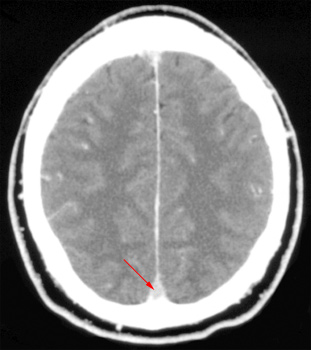

The development of cerebrovascular problems is the most common complication of meningitis. Arterial infarction can occur which often affects the basal ganglia due to the occlusion of small perforating vessels. Hemispheric infarction can also occur due to major vessel spasm. Venous infarctions are also common and can include cortical venous occlusion or the involvement of the superior sagittal sinus.

![]() ![]() The image on the

left shows thrombosis of the superior sagittal sinus (arrow) prior to

the administration of |